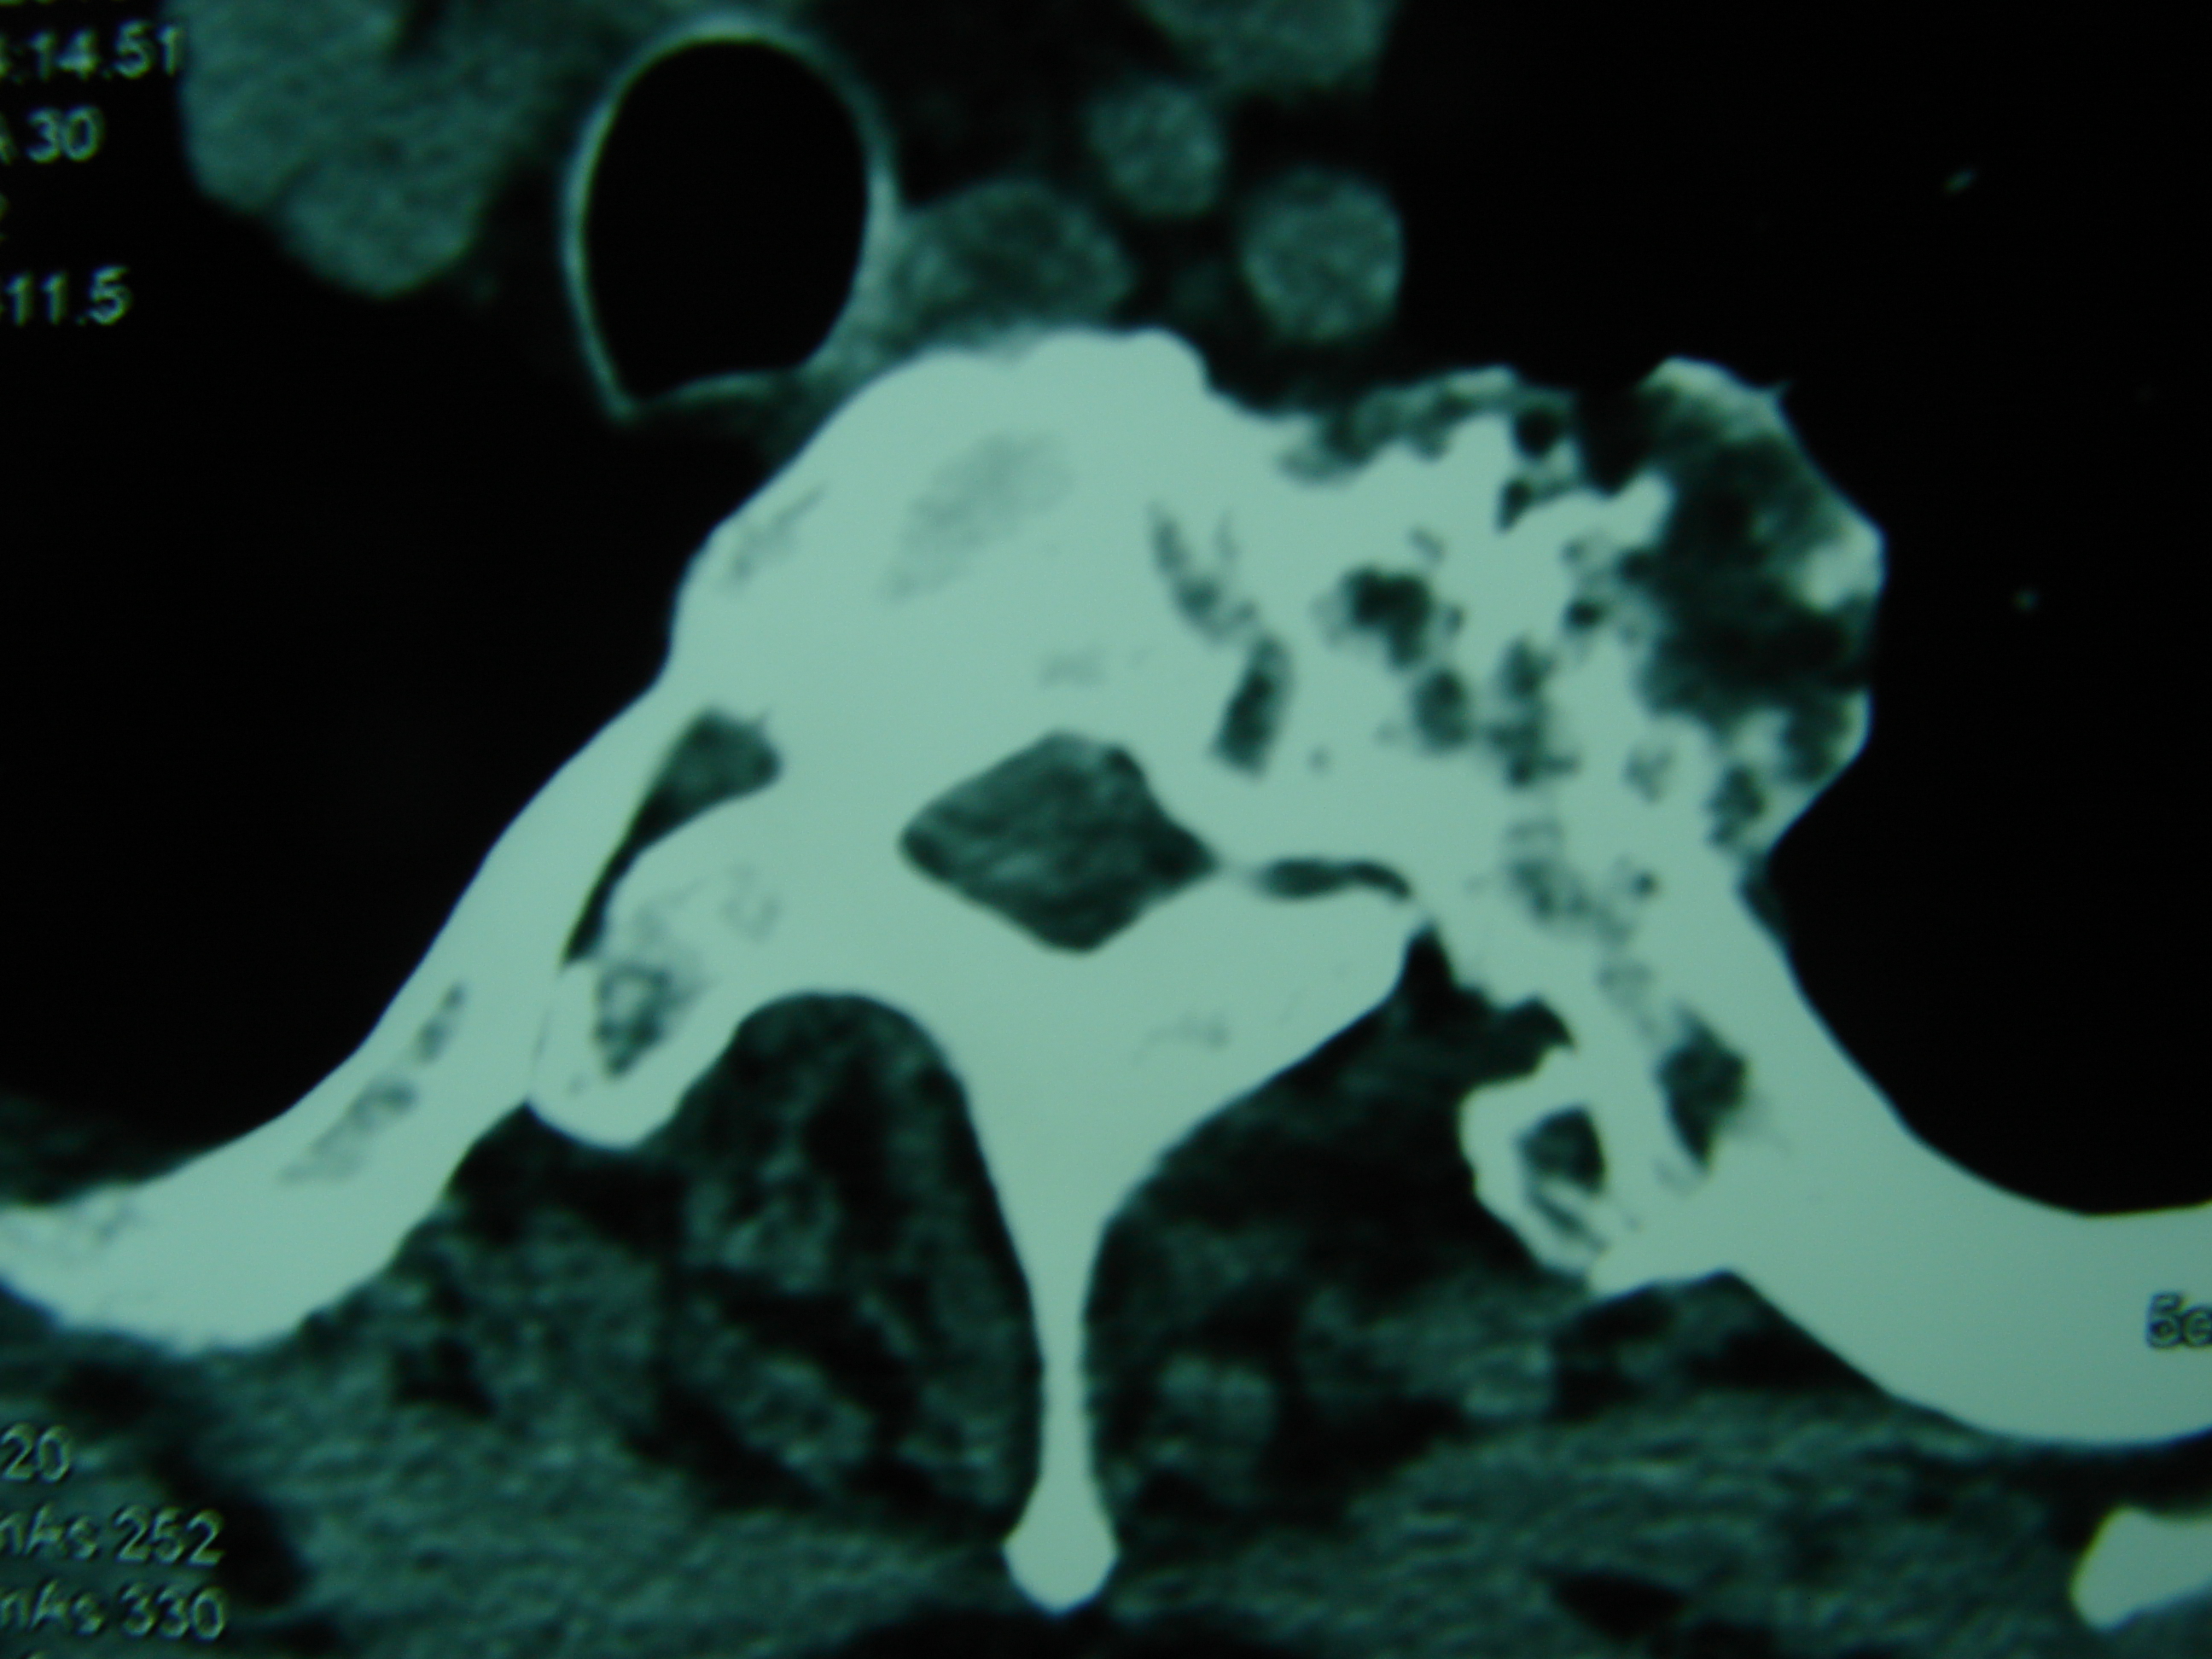

Εικόνα 4 – Προεγχειρητική αξονική τομογραφία

α-σ Αξονική – Εγκάρσια λήψη: Παρατηρείται η παλαιότερη πεταλεκτομή,η εξόστωση του σπονδυλικού σώματος και οι εξοστώσεις σε άλλους σπονδύλους και πλευρές.

τ,υ Μετωπιαία λήψη: Παρατηρείται η παλαιά πεταλεκτομή σε πολλαπλά επίπεδα, η αφαίρεση τμήματος των αριστερών πλευρών και εξοστώσεις σε άλλα σπονδυλικά σώματα.